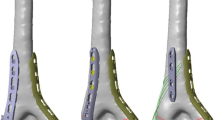

Comminuted olecranon fractures (type Mayo IIb) [11,12,13] were created by an osteotomy in synthetic ulnar bones (Sawbones 3426, Sawbone®, Sweden) [14, 15]. Therefore, the bones were clamped in a custom-made device and the osteotomy was performed by an oscillating saw (PARKSIDE®, Germany) [12]. The fractures were then stabilized in two different ways: in group one, a double-plate osteosynthesis with low-profile locking plates (curved proximal ulnar plates 2.8, Medartis®, Switzerland) was used (Fig. 1a, b). In group two, an olecranon locking plate (LCP 3.5, DePuy Synthes, Johnson & Johnson, Germany) was placed dorsally at the olecranon (Fig. 1c, d. The low-profile locking plates were contoured to the bone without damaging a screw hole by the usual devices served by the company. The position of the plates was performed according to manufactural recommendations: the double plates were fixed at both sides of the proximal ulna with angle-stable screws placed in 90° angle to each other from both sides. Distally, the two plates ended alternated to each other. The proximal fracture fragment was fixed with four angle-stable screws, the wedge fracture fragment with three screws and the distal ulna with seven screws like in usual clinical practise and recommended in literature [7]. In group two, no contouring of the plate to the bone was needed. The LCP was placed ‘classically’ at the dorsal side of the ulna with three angle-stable screws in the proximal, two screws (one angle-stable) in the wedge and four in the distal fracture fragment. Screw length and placement in both groups followed the recommendation of both manufacturers with attention to regular fixation of all fracture fragments and no interaction between the distal shaft screws and the axially to the ulna shaft placed screws from the apex of the olecranon. All osteosyntheses were performed by the same senior orthopaedic surgeon and correct implant positioning was verified radiologically in all specimens.